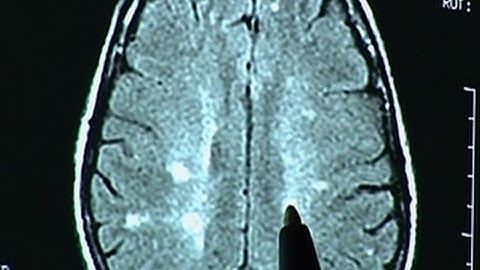

Controlling Multiple Sclerosis with Vitamin D?